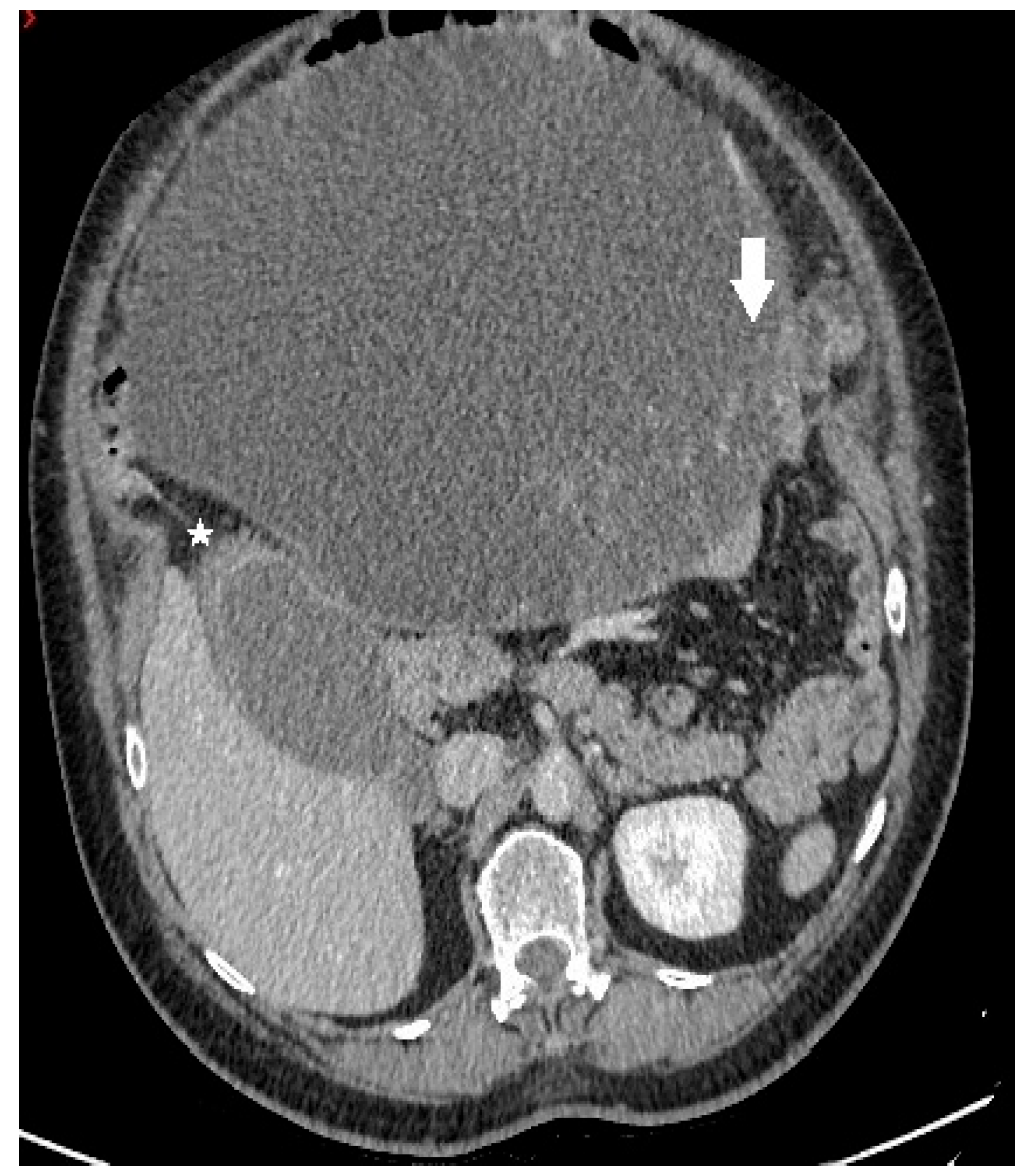

A 68-year-old female patient was admitted to our department due to increasing symptoms of abdominal bloating over the past four months. Other symptoms associated with ovarian cancer were denied by the patient. The patient’s medical history included surgery due to a rupture of an ovarian cyst, while a right adnexectomy was performed 43 years ago. Further, she had hypertension and glaucoma after antihypertensive therapy (Presolol, Asupt, Xalacon). Preoperative CT examination of the abdomen and pelvis confirmed the presence of a tumor in the abdomen and pelvis with a diameter of 335 mm × 275 mm × 345 mm. According to the CT features, the tumor was displacing the surrounding structures, albeit without signs of their infiltration. Initially, the tumor corresponded to left ovarian cystadenocarcinoma (Figure 1, Figure 2 and Figure 3). No intraluminal pathological changes were detected during upper flexible endoscopy and colonoscopy.

Figure 1.

Axial contrast-enhanced CT image demonstrates a predominantly cystic mass, with enhancing papillary projections (white arrow) arising from the left adnexa (not shown). Notice markedly thickened gallbladder wall with alternating areas of high (white star) and low attenuation, giving a striated appearance with mucosal defect—CT signs of acute gangrenous cholecystitis.